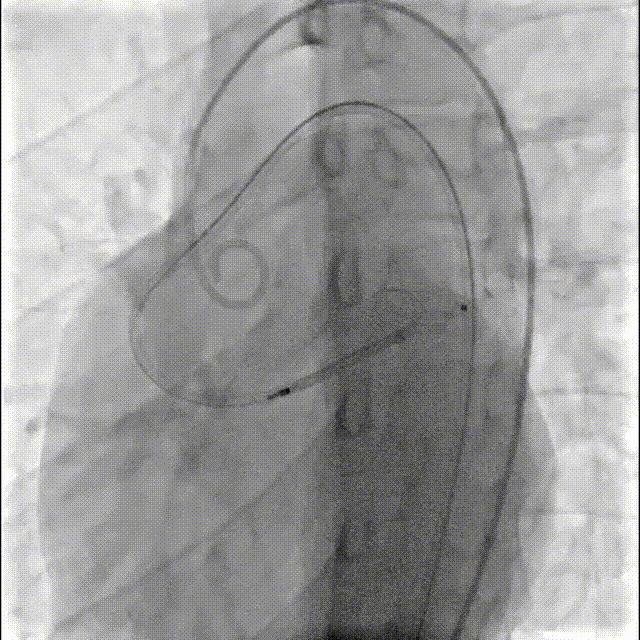

主动脉根部造影显示粗大右冠并分流至左心室显影。

经右侧股动脉在5F单弯导管引导下将260cm泥鳅导丝送至右冠状动脉开口,导丝序贯通过瘘口-左心室-主动脉瓣-升主动脉,

经左侧股动脉在MPA导管引导下将抓捕器放置于无名动脉,抓捕泥鳅导丝,建立轨道